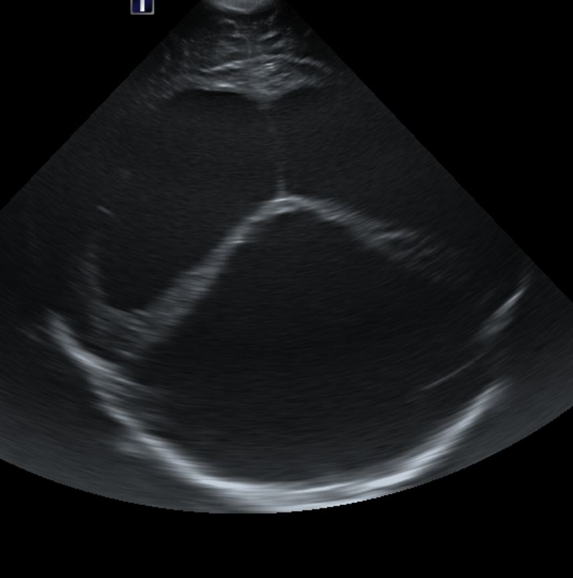

Info Images Findings Impression Reco/Acuity Case Images View Images / Launch Visage Case Notes History Full term infant. We are asked to evaluate posterior fossa cyst. Exam Gray scale and Doppler Ultrasonographic examination of the head. Prior Study N/A Dicom View Reference Material

Section 1 Submit Findings Case149 Findings Brain The brain is immature. Yes No There is under-sulcation and open sylvian fissures. Yes No There is/are multiple hypoechoic areas in the periventricular white matter. Yes No There is/are multiple hyperechoic areas in the periventricular white matter. Yes No There is diffuse cerebral edema with diffusely increased echogenicity of the brain parenchyma and loss of grey white matter differentiation. Yes No The thalami/basal ganglia are hypoechoic. Yes No There is periventricular calcification. Yes No There is intra-parenchymal calcification. Yes No CSF spaces/ventricular system There is a prominence of the extra axial fluid spaces. Yes No There are debris/septations in the extra axial fluid spaces. Yes No There are debris/septations in the ventricles. Yes No There is a subdural collection on the right/left side. Yes No There is prominence of the ventricular system. Yes No There is an asymmetry of the ventricular system. Yes No There is a cavum septum pellucidum. Yes No There is a midline shift towards right/left. Yes No The choroid plexus is bulky/lobulated. Yes No There is a choroid plexus cyst measuring… Yes No There are debris/clots in the occipital horn. Yes No There is a posterior fossa cyst measuring… Yes No The tentorium is elevated/depressed. Yes No The lateral ventricle/s are dilated. Yes No The third ventricle is dilated. Yes No The 4th ventricle is dilated. Yes No There are pseudo cysts. Yes No Germinal matrix hemorrhage (Only in the premature infants): Please do not answer if the patient is a full term. There is a germinal matrix hemorrhage, consistent with a grade I hemorrhage. Yes No There is an intraventricular extension consistent with a grade II hemorrhage. Yes No There is an intraventricular extension with the dilatation of ventricles, consistent with a grade III hemorrhage. Yes No There is an intra-parenchymal extension, consistent with grade IV hemorrhage. Yes No On color Doppler examination, the Resistive index in the anterior cerebral artery is… There is a loss of the diastolic flow on the Doppler exam. Yes No There is altered vascularity on Doppler imaging. Yes No There is an AVM in the region of… Yes No